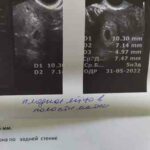

Деформоване пя, гіпертонус по задній стінці

У кого було схоже, пя 7,4 мм, жовтковий мішок 2,6 мм, гіпертонус по задній сненке, плодове яйце деформоване. Це сильно страшно? коли ембріон з'явиться?...